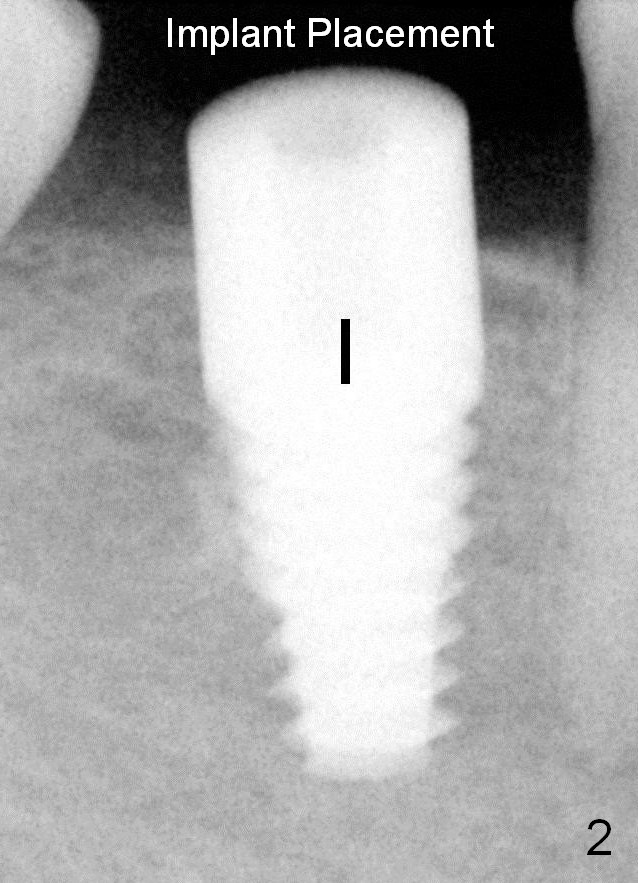

The implant is 6x14 mm (Fig.2).